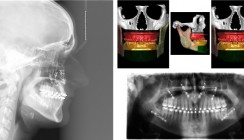

Ritvik, 11 Jahre alt, wird wohl so schnell nicht mehr zu Pfeil und Bogen greifen. Vorerst heißt es: genesen und den vielen Schutzengeln danken! Der kleine Inder rannte während des Schulsportes in die „No enter“-Zone und fing mit seinem Kopf einen Pfeil ab. Dieser durchbohrte seinen Schädel und ragte auf der anderen Seite wieder heraus. Über mehrere Stunden versuchte das Team um Neurochirurg Dr. Jeevan Rajput das Fluggeschoss endoskopisch zu entfernen, mit Erfolg. Die OP verlief ohne Komplikationen und ohne neurologische Folgen für das Kind. Dem kleinen Glückspilz Ritvik geht es mittlerweile wieder prächtig, berichtet die Hindustan Times. Seinem Hobby, dem Bogenschießen möchte er schon bald wieder nachkommen.